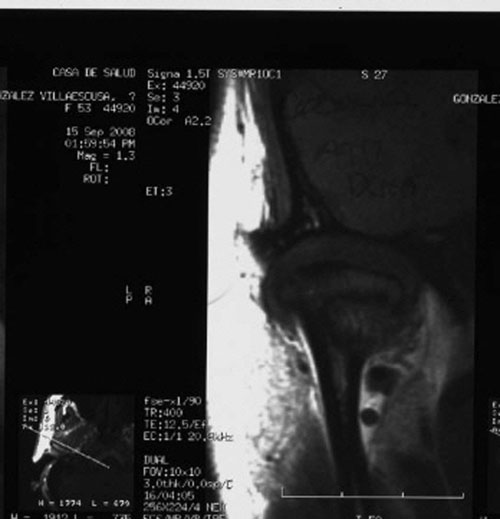

RMN de ATMs (17-09-2008): Dentro de la normalidad.

– ATMs dentro de la normalidad.

PRUEBAS DIAGNOSTICAS COMPLEMENTARIAS:

REF. 3B